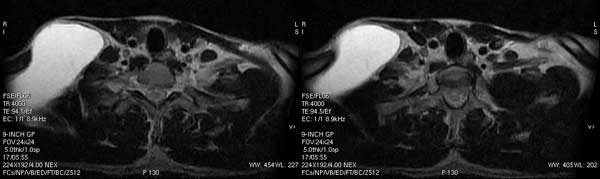

锁骨上窝淋巴管囊肿

锁骨上窝 囊肿病例